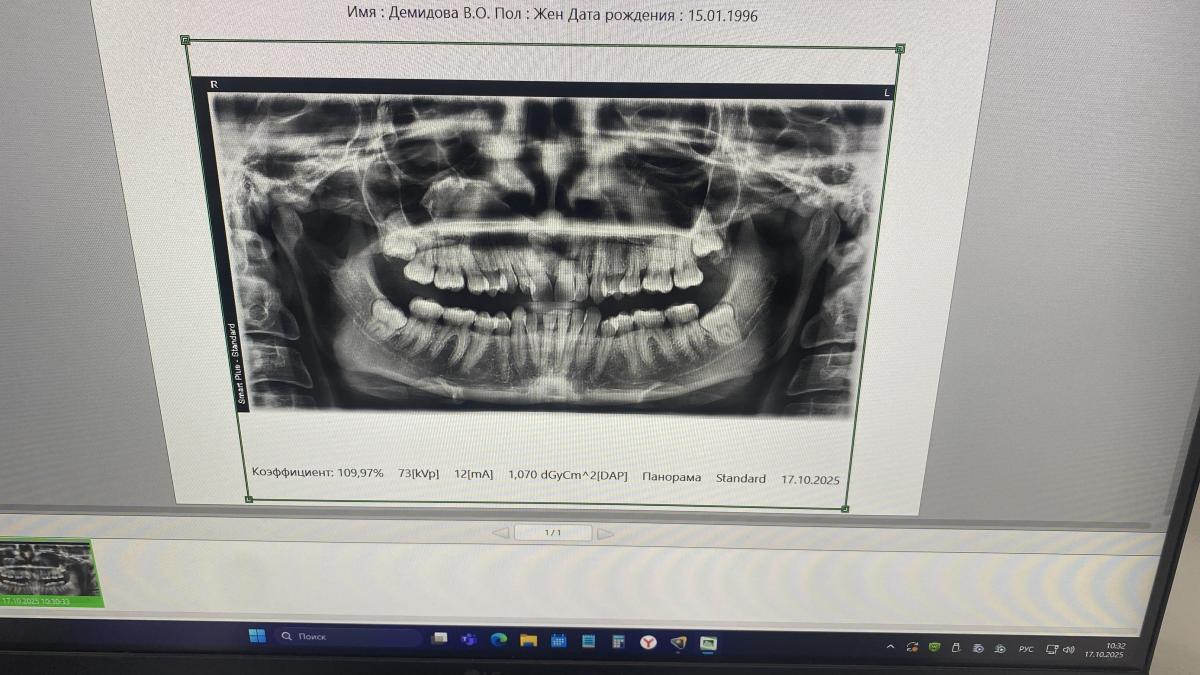

Здравствуйте, 3 месяца назад поставила, брекеты , отказалась на свой риск от удалить 8 сверху , теперь думаю зря , стоит ли удалять ?, и сложная будет операция ?

добрый день! Опираясь только на представленный снимок, сложно сделать однозначный вывод. Нужен еще визуальный осмотр и другие снимки. Для опытного хирурга не бывает сложных удалений, это обычная практика- достать зуб. Для пациента- любое удаление это травма и дискомфорт. Главное правильно принять решение, и правильно выбрать тактику лечения